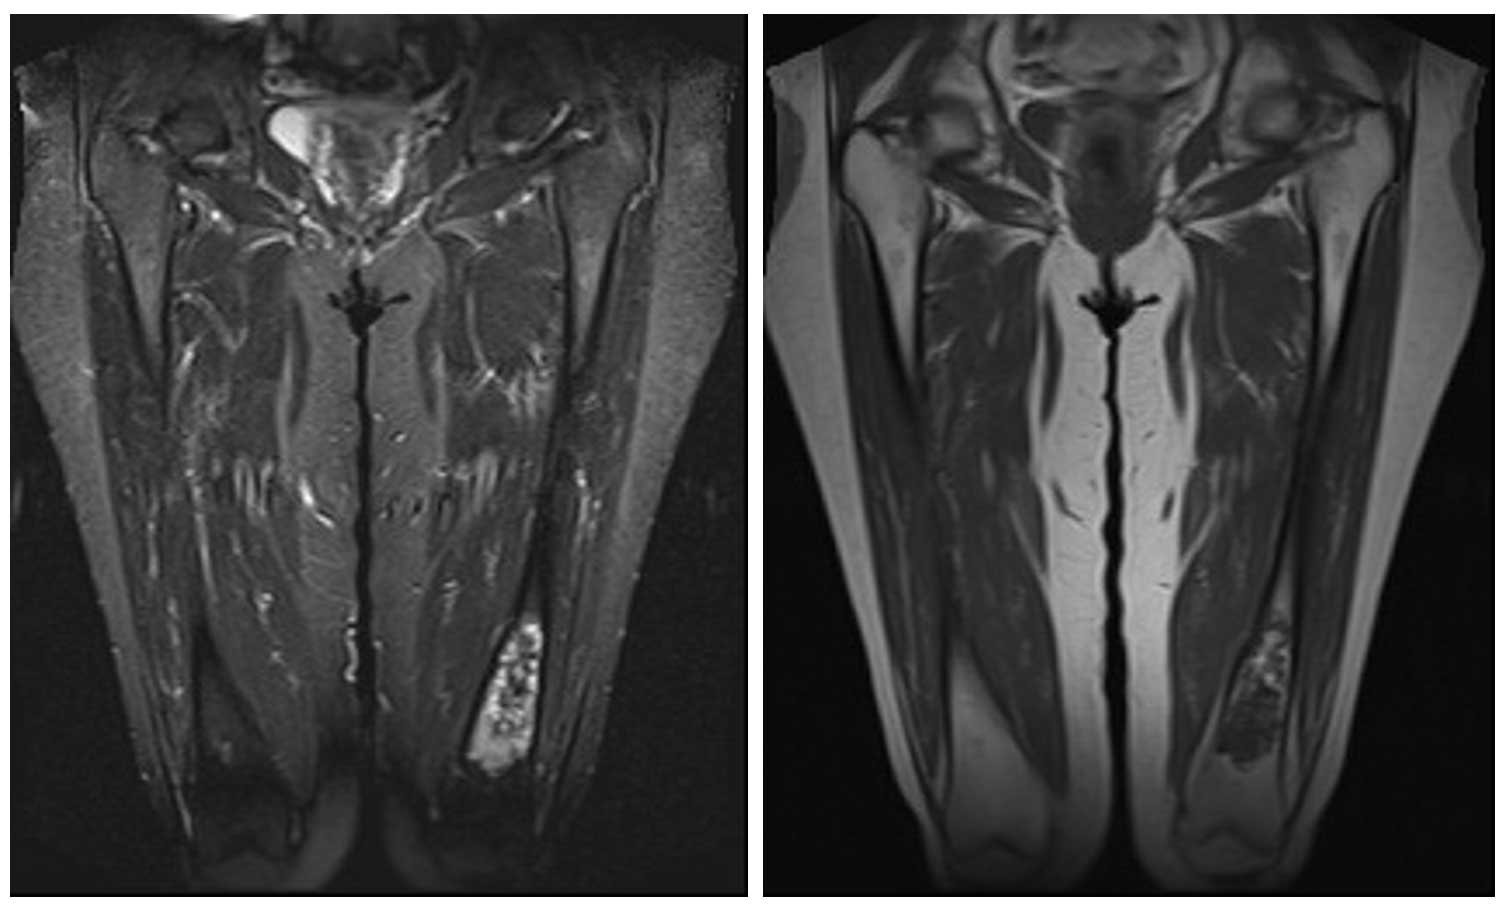

Ameliyat Öncesi: MR’da kemiğin içini dolduran kortekste incelmeye neden olan heterojen kitle görülmekte.